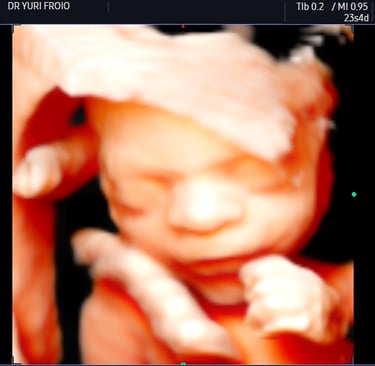

Exames de Ultrassonografia

Oferecemos ultrassonografia geral, morfológico, ecografia vascular e dermatológica com alta precisão e qualidade.